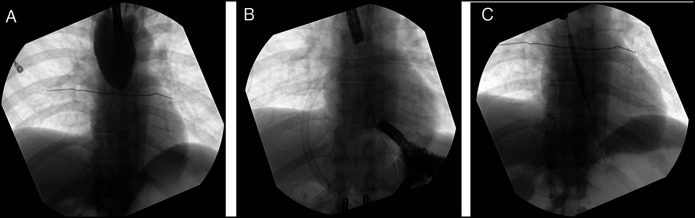

The combined antegrade and retrograde endoscopic rendezvous technique effectively restores patency for esophageal short-segment obstructing strictures (<3 cm). However, long-segment strictures typically require complex surgery, with endoscopic management rarely reported. We report a 44-year-old man with a 9 cm esophageal obstruction due to peptic stricture who was at high risk of esophageal resection due to severe cardiac disease and prior abdominal surgeries. He underwent successful recanalization using a rendezvous technique. Serial dilations with subsequent esophageal stenting restored luminal patency. This case highlights the feasibility of an endoscopic approach as a safe and effective alternative to surgery in long-segment peptic strictures.

Abstract Image